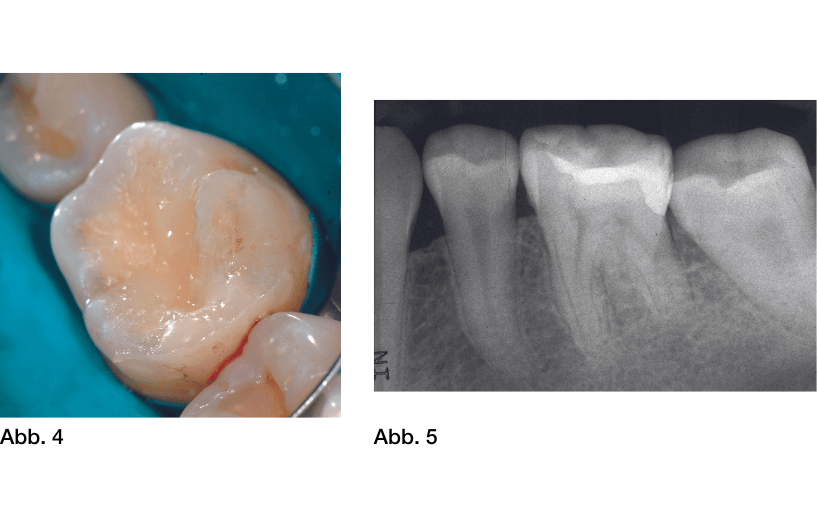

Weil über dem vitalen Pulpagewebe nur eine minimale Dentinschicht verbleibt, besteht die Gefahr, dass es über die Dentintubuli zu einer irreversiblen Entzündung der Pulpa kommt: einerseits durch verbliebene oder bereits in das Gewebe eingedrungene Mikroorganismen, andererseits durch zytotoxische Bestandteile aus Füllungsmaterialien, die durch das dünne Restdentin diffundieren können.[33] Pulpanahes Dentin sollte daher exkaviert, desinfiziert und mit einem Überkappungsmaterial bakteriendicht versiegelt werden, das zudem idealerweise die Bildung von tertiärem Dentin stimuliert.[47] (Abb. 1-5)